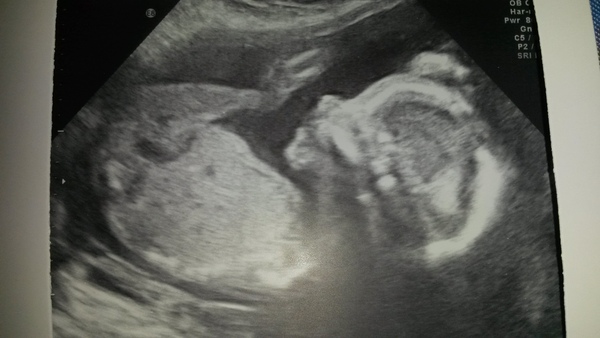

Yay greedy, lovely scan pic too!

Greedy that's gorgeous Grin

Greedy what a lovely clear scan photo :-)

Greedy how lovely,your picture is so clear.